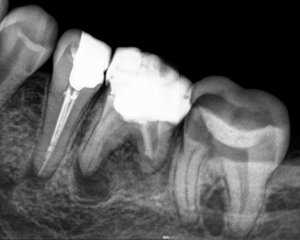

У меня обнаружили 2 кисты на 36 зубе. На одном корне киста маленькая, на втором большая. Снимок прилагается. Врач-терапевт сначала сказал, что нужно удалить кисту, а потом сказал лечить. Просверлил зуб, оставил открытым, сказал полоскать солевым раствором и принимать Кетарол.

У меня возникли сомнения по этому поводу. Посоветуйте, что лучше сделать: продолжить лечение таким методом, вырезать кисту или удалить зуб? Высока ли вероятность того, что могут плохо запломбировать каналы и инфекция снова начнёт развитие? Если сейчас спасти зуб, то с годами всё равно его нужно будет удалять?

Не мучайте себя и не тратьте время и деньги, зуб удаляется.